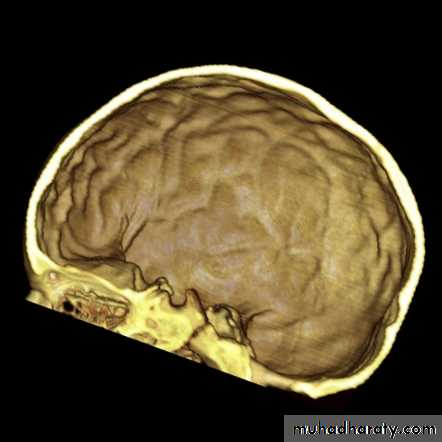

Copper-beating’ marking